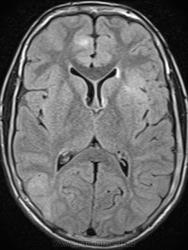

Это болезнь Бурневилля - одна из форм факоматозов?

Да, это болезнь Бурневилля-Прингла, один из видов факоматоза. Врожденное заболевание, развивается из-за нарушений в одной из хромосом.

На УЗИ выявлены множественные ангиомиолипомы почек.